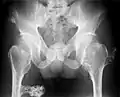

Hereditary multiple osteochondromas (HMO), also known as hereditary multiple exostoses, is a disorder characterized by the development of multiple benign osteocartilaginous masses (exostoses) in relation to the ends of long bones of the lower limbs such as the femurs and tibias and of the upper limbs such as the humeri and forearm bones. They are also known as osteochondromas. Additional sites of occurrence include on flat bones such as the pelvic bone and scapula. The distribution and number of these exostoses show a wide diversity among affected individuals. Exostoses usually present during childhood. The vast majority of affected individuals become clinically manifest by the time they reach adolescence.[1][2] A small percentage of affected individuals are at risk for development of sarcomas as a result of malignant transformation. The incidence of hereditary multiple exostoses is around 1 in 50,000 individuals.[3] Hereditary multiple osteochondromas is the preferred term used by the World Health Organization.

A noticeable lump in relation to an extremity may be the first presenting symptom. Multiple deformities can arise, namely coronal plane deformities around the knees, ankles, shoulders, elbows, and wrists. For example, genu valgum (knock knees), ankle valgus, ulnar bowing and shortening, and radial head subluxation are encountered. The majority of affected individuals have clinically manifest osteochondromas around the knee. Forearm involvement in HMO is considerable.[1][4] Furthermore, short stature may occur and is generally disproportionate. Such manifestations usually result from disruption of physeal growth especially that osteochondromas typically arise at the metaphyseal ends of long bones in close proximity to the physis.[1][4] Intra-articular osteochondromas of the hip can induce limitation of range of motion, joint pain and acetabular dysplasia.[2] Likewise joint pain at other locations and neurovascular compression can occur. Furthermore, functional disability in regard to activities of daily living can be a presenting feature. Spinal deformity pain or neurological compromise should arouse suspicion of involvement of the vertebrae.[3]

The diagnosis of HMO is based upon establishing an accurate correlation between the above-mentioned clinical features and the characteristic radiographic features. Family history can provide an important clue to the diagnosis. This is supplemented by testing for the two genes in which pathogenic variants are known to cause HMO namely EXT1 and EXT2. A combination of sequence analysis and deletion analysis of the entire coding regions of both EXT1 and EXT2 detects pathogenic variants in 70–95% of affected individuals.[3][4] The hallmark of radiographic diagnosis is the presence of osteochondromas at the metaphyseal ends of long bones in which the cortex and medulla of the osteochondroma represent a continuous extension of the host bone. This is readily demonstrable in radiographs of the knees.[3][1]